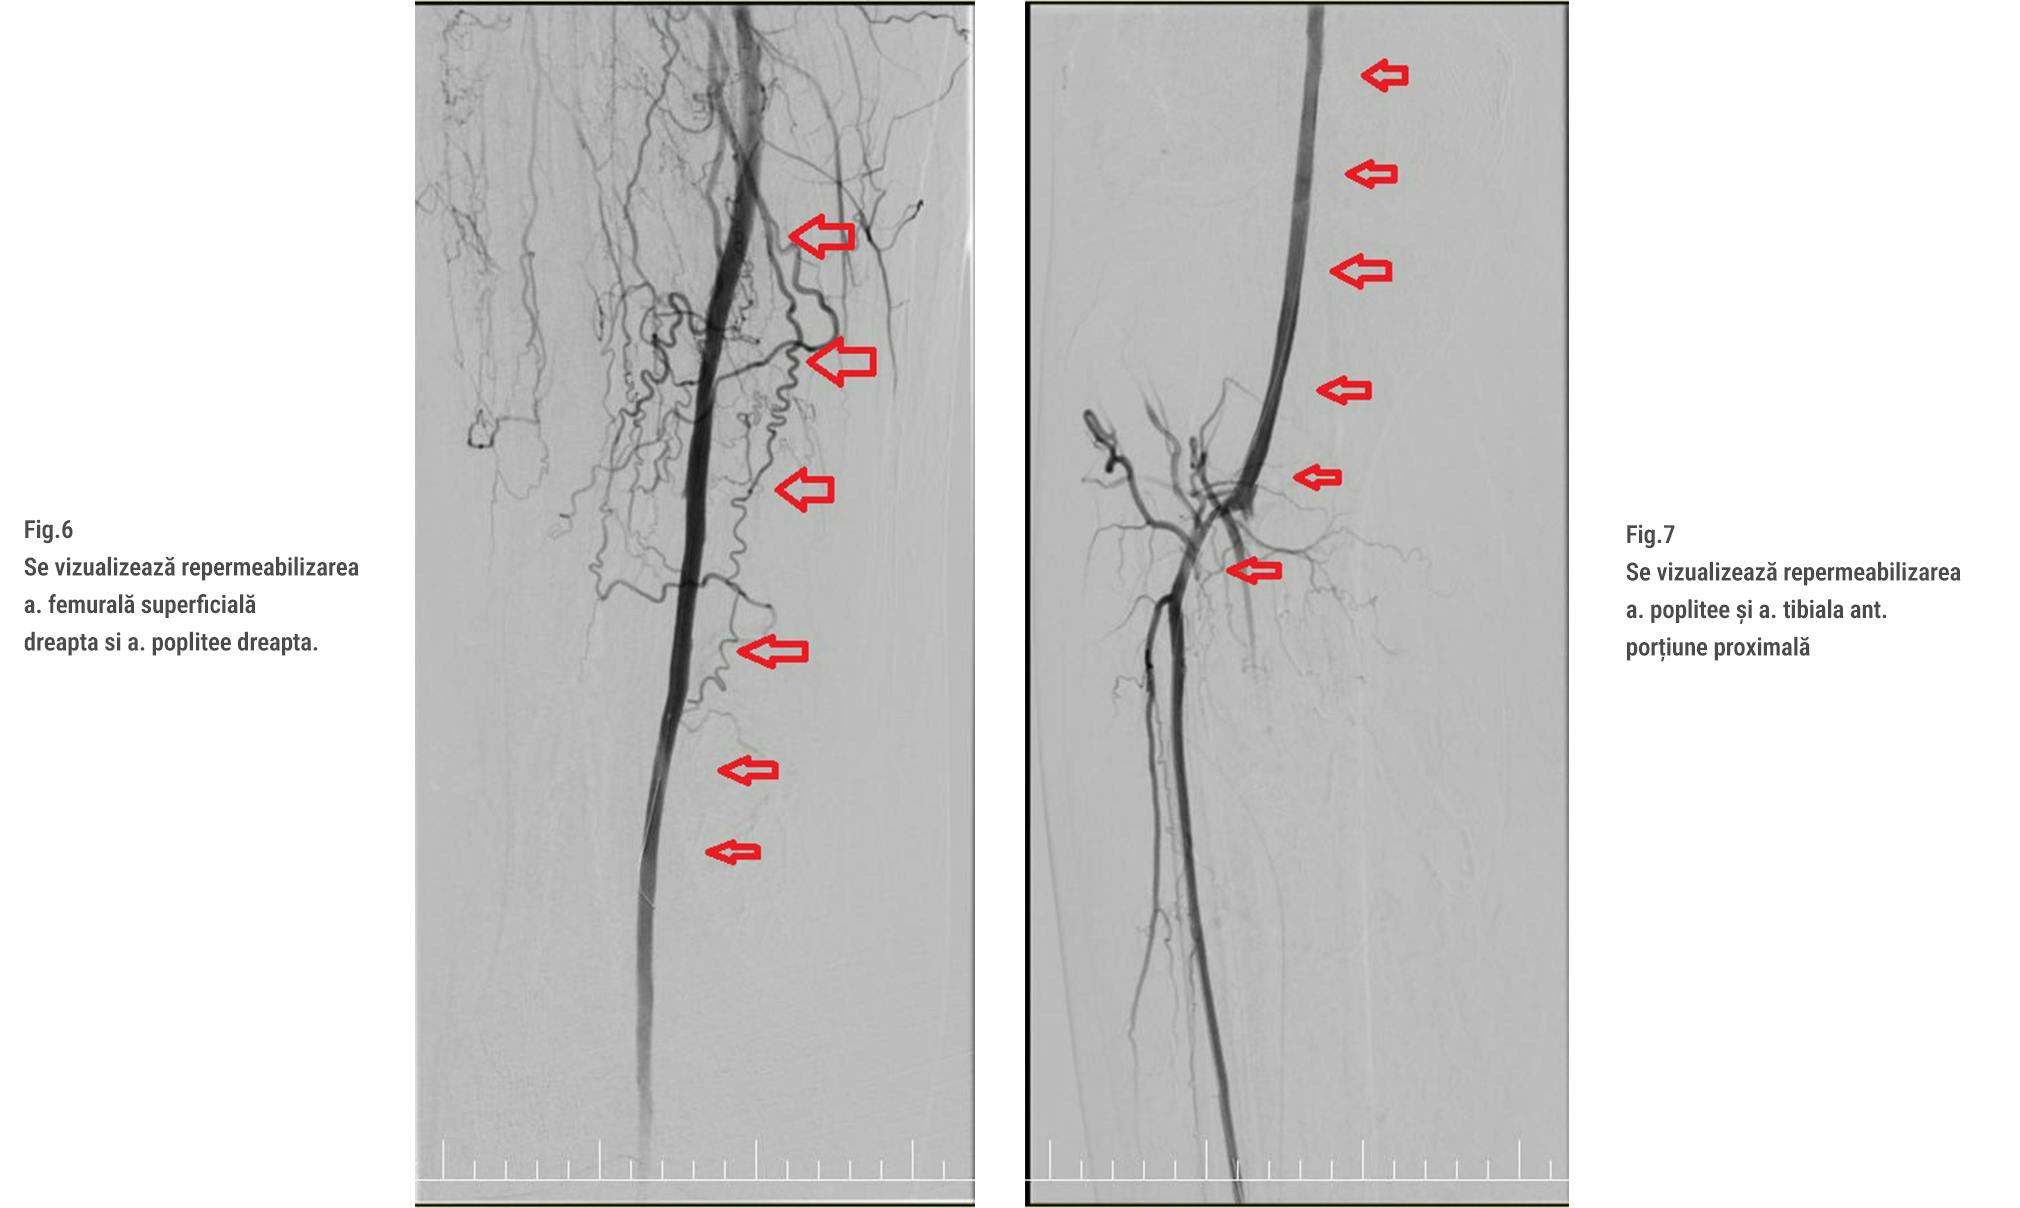

Procedura CTO (Chronic Total Occlusion) reprezintă o tehnică avansată utilizată pentru tratarea arterelor complet blocate. În acest caz, s-a utilizat un ghid special și un microcateter pentru a traversa zona blocată. Echipa medicală a realizat dilatarea succesivă a arterelor femurale superficiale, poplitee și tibiale anterioare folosind baloane de diverse dimensiuni și presiuni. Această procedură complexă a necesitat utilizarea unor echipamente avansate și o coordonare precisă pentru a obține rezultate optime. (Fig. 6,7)